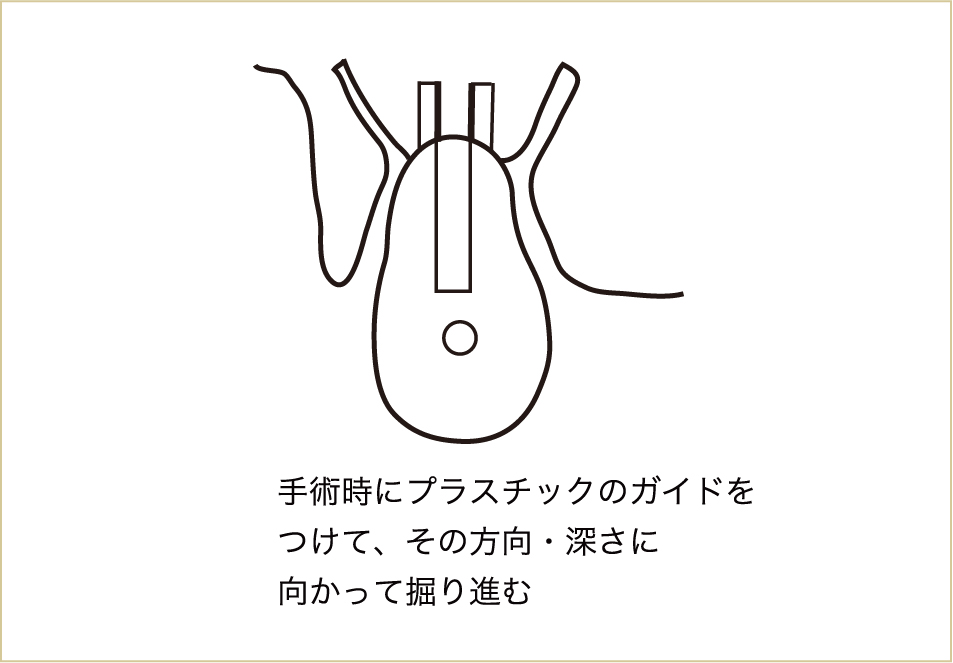

CTによって、かなり高い精度で骨の構造が立体的に把握できるようになりました。最近では、このCTのデータをパソコン上でコンピューターガイドシステムとして手術のシミュレーション計画を立て、実際の外科手術を行う際に、反映させることもできるようになってきています。

CT上でインプラントを立てる位置、方向、長さ、深さなどを決定して、それを誘導するマウスピースのようなもの(サージカルテンプレートという)をつくり、それをガイドとして実際の手術を行います。

プラスチックと金属でできたサージカルガイド(マウスピースのようなもの)を用いて手術を行うことで、術前に診断した箇所にインプラントを埋入することができる。

これまで術者の感覚のみで行っていた手術に比べ、CTの画像データを用いて診査することで、様々な偶発症を予防し、治療効果を上げることもできるようになり、安全性がより高まったといえます。